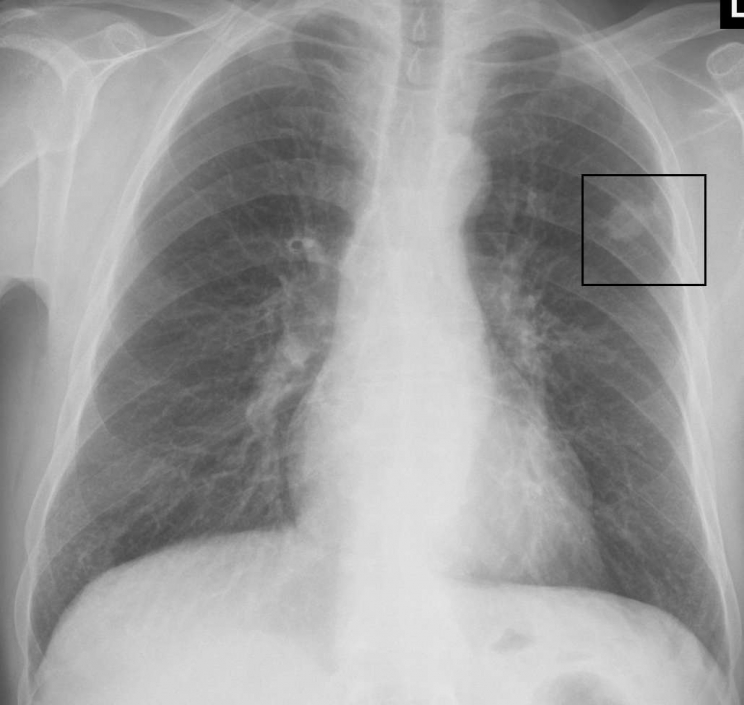

Quando l'organismo si rende conto di poter far poco in questa situazione, crea delle vere e proprie "barricate" per far sì che il batterio rimanga confinato in un certo punto, barricate che crescono sempre di più (e divengono dei tubercoli, da qui il nome tubercolosi) perché proprio, contro i micobatteri, non c'è nulla da fare.

I noduli crescono sempre di più, causando problemi alla digestione e alla respirazione, perché tolgono spazio alle normali operazioni vitali. A volte poi si spezzano (soprattutto a causa dei colpi di tosse), e da un nodulo se ne formano due, che continuano a crescere, e così via, fin quando la situazione diventa intollerabile.